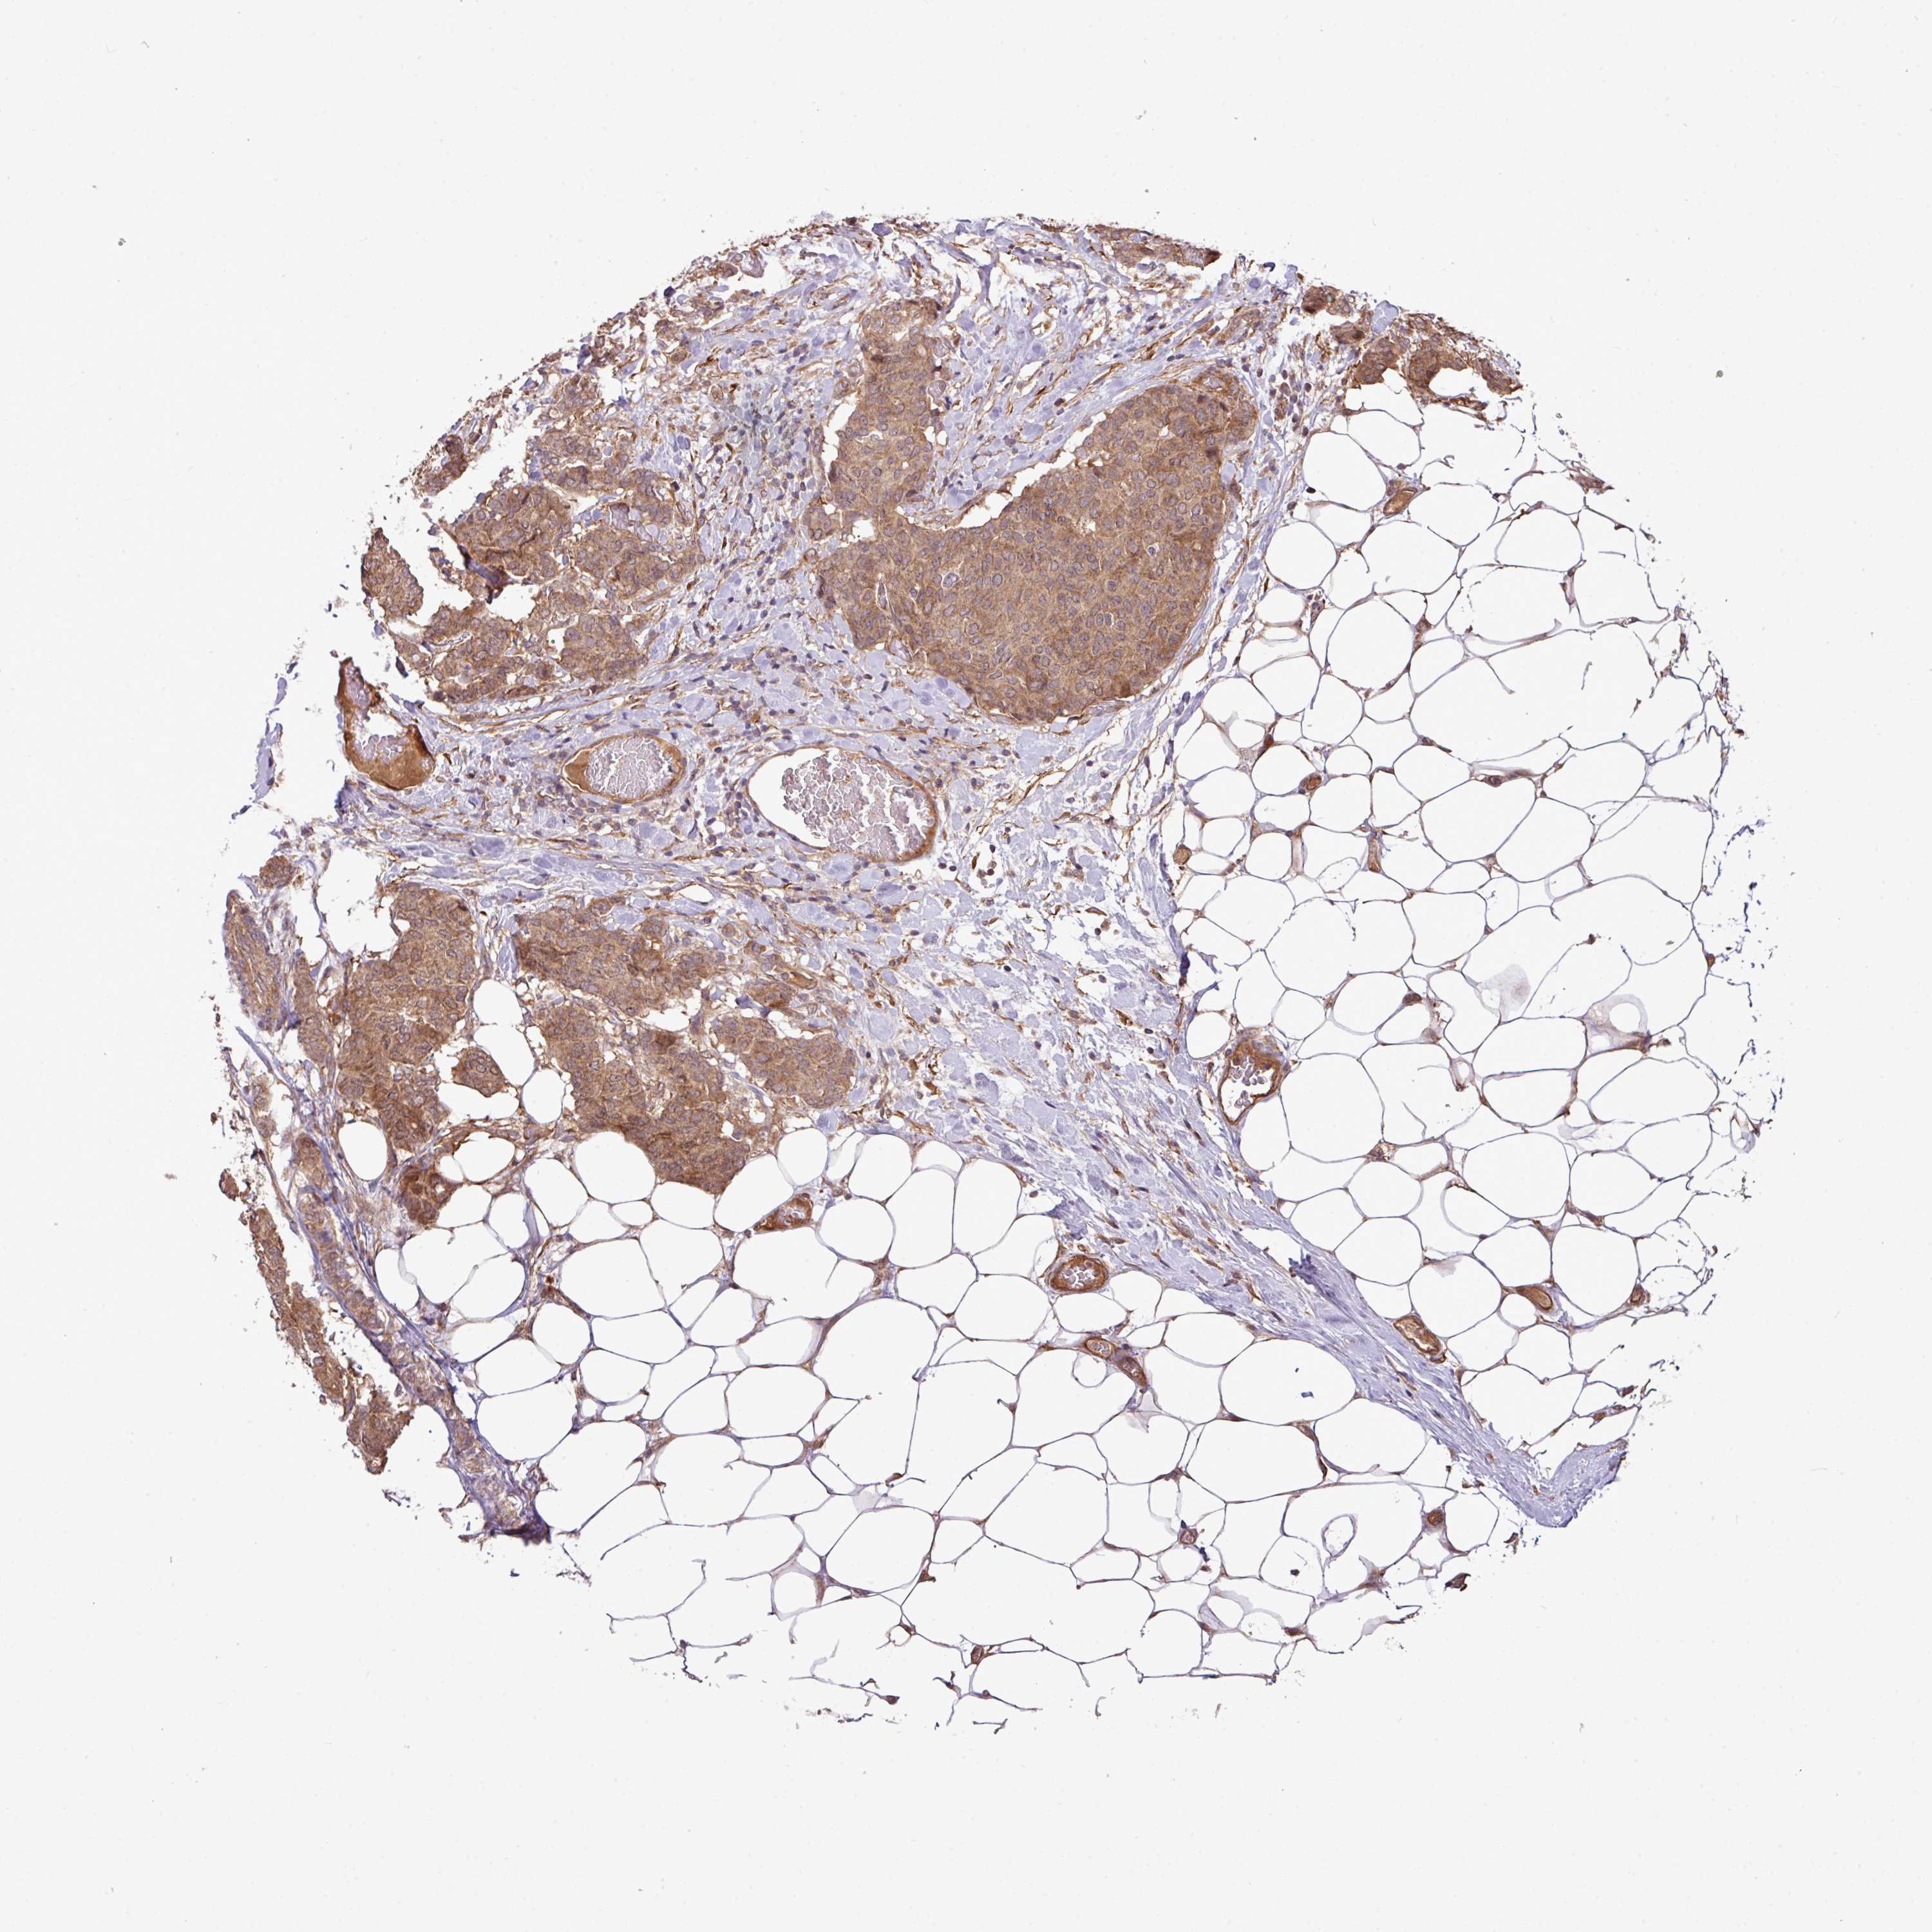

BRCA TCGA BRCA VALIDATION PROTEIN EXPRESSION

ANTIBODIES

AND

VALIDATION